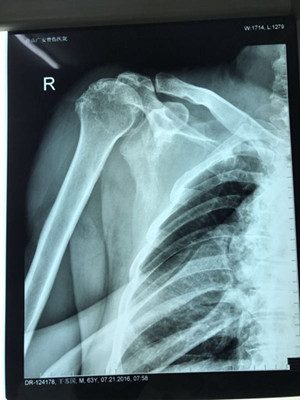

【重磅】廣安醫(yī)院成功開展國際先進(jìn)的反式肩關(guān)節(jié)置換術(shù)

日前,廣安醫(yī)院成功開展了國際先進(jìn)的反式肩關(guān)節(jié)置換術(shù)。

近日,在舟山廣安骨傷醫(yī)院關(guān)節(jié)科病房里,60多歲的干大伯神情怡然,通過反式肩關(guān)節(jié)置換術(shù),他長(zhǎng)達(dá)半年多的嚴(yán)重肩袖損傷終于獲得重建,肩部的頑固性疼痛也隨即消失。

據(jù)了解,干大伯半年前因外傷導(dǎo)致頸椎外傷伴截癱,右肩關(guān)節(jié)脫位伴巨大肩袖斷裂,曾在廣安醫(yī)院接受頸椎手術(shù),術(shù)后恢復(fù)良好。后來,干大伯要求進(jìn)一步對(duì)肩關(guān)節(jié)進(jìn)行治療。廣安醫(yī)院副院長(zhǎng)危立軍及運(yùn)動(dòng)醫(yī)學(xué)科主任羅軍對(duì)其進(jìn)行詳細(xì)檢查后,認(rèn)為干大伯的右肩存在巨大不可修復(fù)肩袖撕裂伴嚴(yán)重的關(guān)節(jié)炎,肩袖的脂肪浸潤達(dá)到四級(jí),治療上有一定的挑戰(zhàn)性,只能通過特殊類型的人工肩關(guān)節(jié)——反式全肩人工關(guān)節(jié)來重建關(guān)節(jié)功能。

經(jīng)過前期準(zhǔn)備,危立軍副院長(zhǎng)及羅軍主任帶領(lǐng)手術(shù)專家團(tuán)隊(duì)為干大伯實(shí)施反式人工肩關(guān)節(jié)置換術(shù)。經(jīng)過一個(gè)多小時(shí)的手術(shù)時(shí)間,干大伯被推出了手術(shù)室。手術(shù)非常順利,刀口小,約10厘米,術(shù)后恢復(fù)快。第二天查房時(shí),干大伯便能佩戴特制的肩肘墊起床活動(dòng),肩關(guān)節(jié)劇痛也大大緩解。

據(jù)悉,反式肩關(guān)節(jié)置換術(shù)在國際上屬于先進(jìn)技術(shù),目前國內(nèi)只有少數(shù)醫(yī)院開展,此次手術(shù)的成功開展填補(bǔ)了廣安醫(yī)院在該項(xiàng)技術(shù)領(lǐng)域的空白,同時(shí)標(biāo)志了該院在人工關(guān)節(jié)置換技術(shù)方面又上了一個(gè)新階。